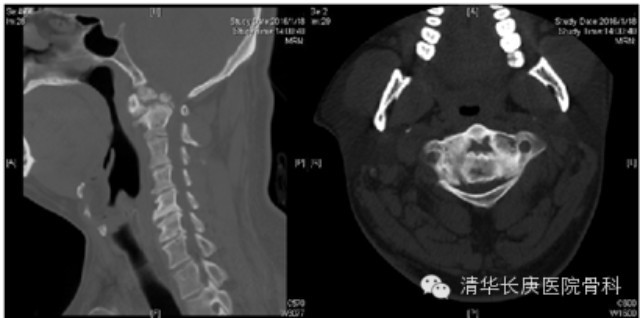

清华长庚医院2月21日电(骨科 宋飞)近日,北京清华长庚医院骨科脊柱专业组收治一名复杂上颈椎畸形患者,先天性枢椎齿状突发育不良伴寰枢椎脱位,出现进行性加重的脊髓损害表现(图1)。骨科主任肖嵩华教授主刀为患者施行联合前后路手术:前路经口减压松解、减压、齿状突切除,后路寰枢椎椎弓根钉内固定植骨融合。

图1、术前CT:齿突发育不良,增生硬化,高位颈脊髓严重受压,后伸不能复位